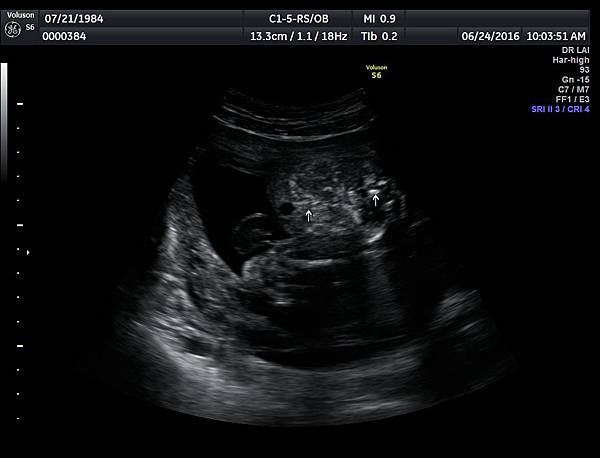

6月24日在我的診所,我幫一位懷孕22週31歲的孕婦看高層次超音波,發現胎兒的腸子很白,形狀也特別的怪( 附圖 1~12 ),我建議她做進一步相關的檢查,包括抽羊水檢查等等。